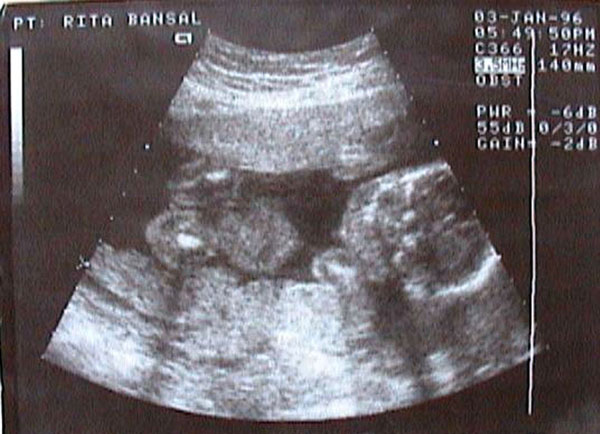

A?fetal ultrasound?image. [Photo/IC]??? |

Serious gender imbalances occurred after the late 1980s when B-ultrasound technologies used for sex-selection were widely available in China. As a result, Chinese couples chose to abort female fetuses following the test, opting for boys to carry forward the family bloodline.